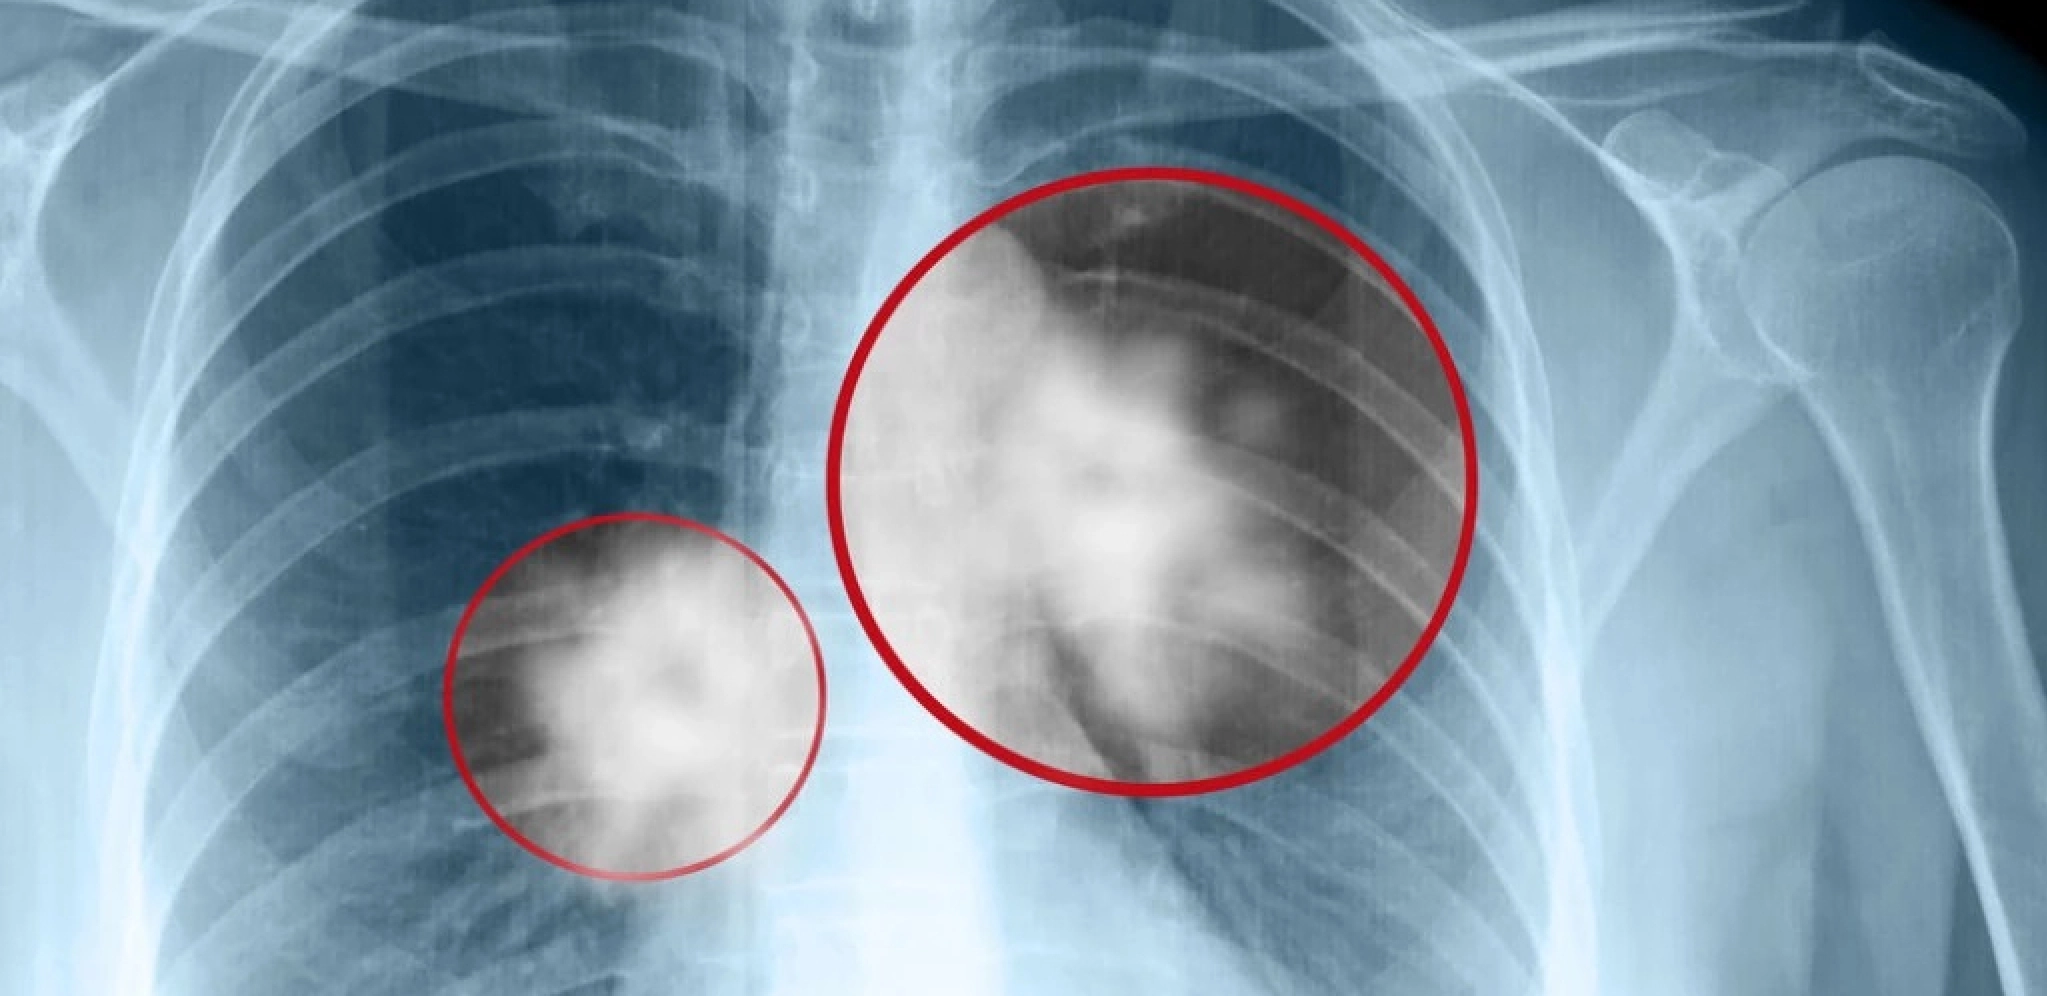

- Karcinom pluća je podmukla bolest, jer u trenutku kada se osete prvi simptomi većina bolesnika je već u metastatskom stadijumu bolesti. Simptomi u početku mogu da budu vrlo nespecifični - kašalj koji duže traje i ne prolazi na primenu antibiotika, prolongirano febrilno stanje, malaksalost, gubitak apetita, bolovi u grudima. Dodatni problem predstavlja činjenica da većinu bolesnika koji obole od karcinoma pluća predstavljaju pušači koji su već navikli na kašalj i iskašljavanje i to ih zavara. Ne primete kada kašalj postane uporniji, izraženiji i promeni intenzitet. Upravo u tom periodu često se izgubi dragoceno vreme, bolest uznapreduje, terapijske mogućnosti se smanje, a prognoza bolesti postane značajno lošija – objasnio je Ass. dr Mihailo Stjepanović, direktor Klinike za pulmologiju UKC Srbije.